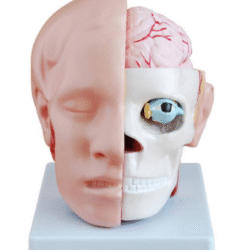

ATL-11 MALE MUSCLES FIGURE INTERNAL ORGANS HARD

The model is an anatomically accurate representation of the human anatomy, complete with superficial and deep musculature, the digestive system, lymphatic system, respiratory system, urinary system, circulatory system, endocrine system, and nervous system. Our model has removable organs and dissectible features for a complete educational experience.

Classification:

Skeleton Models(human bone, muscle, etc.)